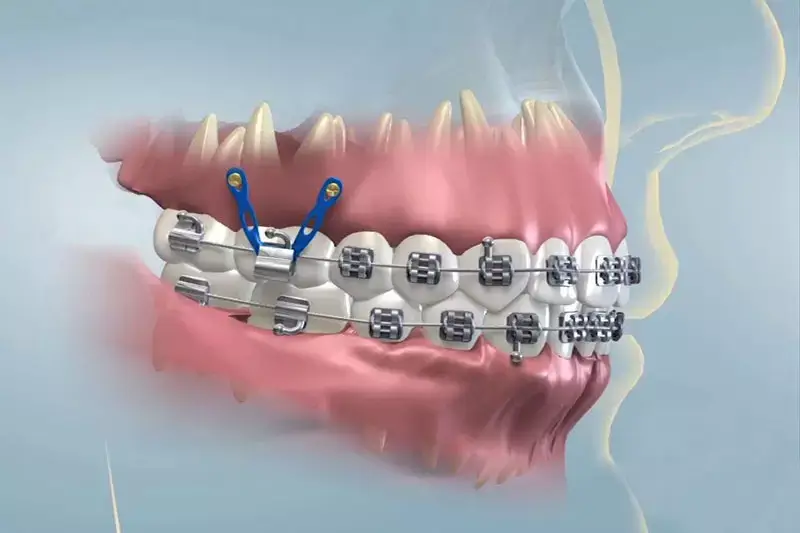

Đóng khoảng bằng minivis

Trong những trường hợp phức tạp, bác sĩ có thể áp dụng phương pháp cắm minivis – một loại vít nhỏ được cắm tạm thời vào xương hàm để tạo điểm neo cố định khi kéo răng. Đây là phương pháp hiện đại, thường được sử dụng trong các trường hợp cần kiểm soát lực kéo chặt chẽ hoặc khi cần đóng các khoảng răng lớn.

Khi có minivis, bác sĩ có thể kéo răng trực tiếp về phía mong muốn mà không làm ảnh hưởng đến các răng khác, từ đó tăng độ chính xác trong quá trình chỉnh nha.

Đóng khoảng bằng minivis